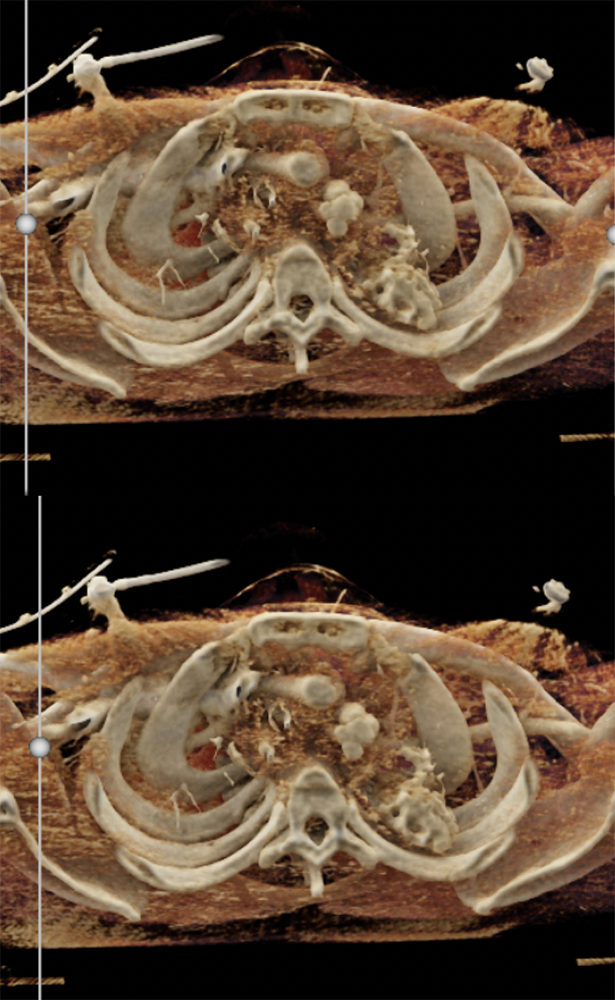

• mediastinal haematoma of venous origin: not all mediastinal bleeding corresponds to aortic injury. The literature describes trauma injuries to the great veins like the superior vena cava. These injuries are rare but they can be life-threatening; • mediastinal haematoma secondary to an extra-aortic injury. It is important to know how to detect abnormalities of the supra-aortic vessels, possibly using 3D reconstruct-ions. These dangerous lesions are a therapeutic challenge. They are often associated with aortic injuries although they can sometimes be isolated. Traumatic injuries of the thoracic aorta: The role of imaging in diagnosis and treatment F.Z. Mokranea et al. Diagnostic and Interventional Imaging (2015) 96, 693—706 |

“Acute aortic injuries are not common in the setting of severe blunt trauma, but lead to significant morbidity and mortality. High- quality MDCT with 2D MPRs and 3D rendering are essential to identify aortic trauma and distinguish anatomic variants and other forms of aortic pathology from an acute injury. Misinterpretation of mimics of acute aortic injury can lead to unnecessary arteriography and thoracic surgery. Since most traumatic injuries occur in the distal arch, radiologists must be cognizant of the range of appearances of variants related to the ductus diverticulum. Cinematic rendering (CR) is a new 3D post-processing tool that provides even greater anatomic detail than traditional volume rendering. In this case series, CR is used to impart to radiologists a better understanding of various anatomic configurations that can be seen with a ductus diverticulum.” MDCT of ductus diverticulum: 3D cinematic rendering to enhance understanding of anatomic configuration and avoid misinterpretation as traumatic aortic injury Steven P. Rowe & Pamela T. Johnson & Elliot K. Fishman Emergency Radiology (2018) 25:209–213 |

”Among these is the ductus diverticulum—a remnant of the ductus arteriosus that arises from the lesser curvature of the aortic arch, which can be mistaken for a traumatic aortic pseudoaneurysm, dissection, or incomplete rupture. The distal aortic arch, and in particular the undersurface, is the most common location for acute traumatic aortic injury. Differentiation of a ductus diverticulum from an aortic injury can be difficult, but it is of paramount importance in order to spare patients the morbidity of unnecessary thoracic surgery. This becomes more challenging in the setting of other thoracic traumatic injury, especially mediastinal hematoma, as demonstrated in this case report.” MDCT of ductus diverticulum: 3D cinematic rendering to enhance understanding of anatomic configuration and avoid misinterpretation as traumatic aortic injury Steven P. Rowe & Pamela T. Johnson & Elliot K. Fishman Emergency Radiology (2018) 25:209–213 |